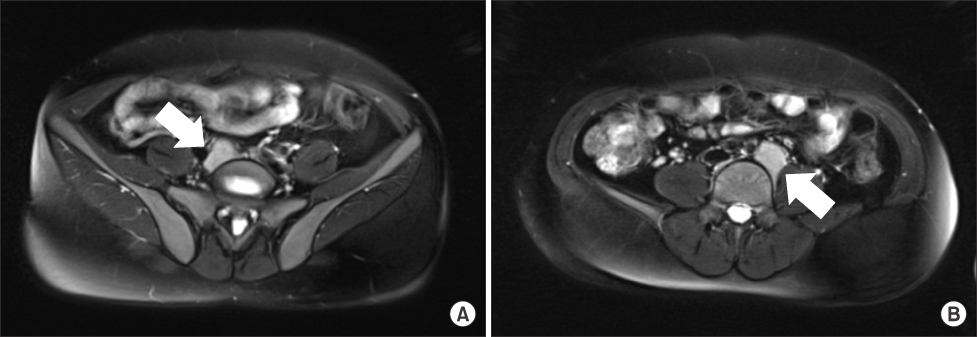

Fig. 1

Abdominal MRI shows two homogeneous enhancing masses in both common iliac area (arrows). (A) Right side. (B) Left side.

Fig. 1 Abdominal MRI shows two homogeneous enhancing masses in both common iliac area (arrows). (A) Right side. (B) Left side.